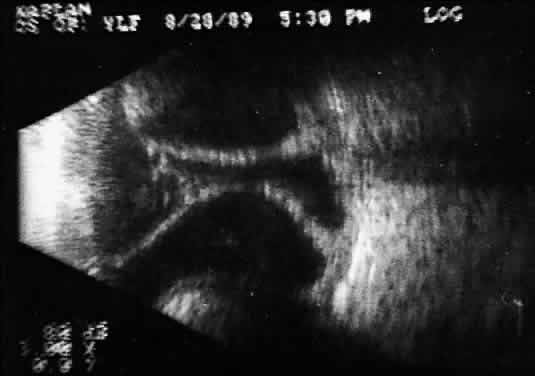

During contact B-scan imaging, each quadrant of the globe is scanned systematically from probe positions that avoid, if possible, any passage of the examining or returning sound through the artifact-inducing lens system (Fig. 8). For the beginner, practice with clear media patients, such as those with total or partial retinal detachment, is essential (Fig. 9). The ultrasonically derived vitreoretinal drawing can then be compared to standard optical examinations. As experience increases, similar but more difficult cases can be attempted. Specifically, B-scan examination of diabetic patients with traction retinal detachments and clear media should be attempted and compared to visually controlled drawings. These self-testing exercises, especially in complex cases, provide the examiner a feeling for his or her level of competence and reliability in 3D thinking. Opaque media cases can then be approached with greater confidence and diagnostic accuracy.

Fig. 9. Contact B-scan: total retinal detachment, anteroposterior view. Characteristic V-shaped appearance with attachment to the optic nerve head.